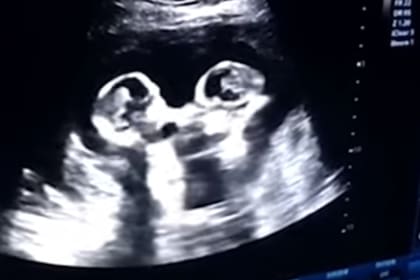

Unas gemelas parecen pelear en el útero de la madre, según captan durante la ecografía

Una madre embarazada de 4 meses asistió a realizarse una ecografía a un centro de salud ubicado en la ciudad china de Yinchuan. Todo transcurria con normalidad hasta que su marido, que filmaba el monitor con el que se realizaba el control de rutina, descubrió que -a juzgar por sus movimientos- sus gemelas parecían estar peleándose.

Tao le explicó al periódico chino The Paper que le parecía divertido ver a sus hijas por nacer como "peleando entre ellas por unas cuantas rondas". La particular escena, que se produjo a fines de 2018, tuvo su continuidad pero en esa ocasión con gestos de cariño. De hecho, el padre de la gemelas, contó que durante otra ecografía realizada al mes siguiente ambas parecían estar abrazándose.

Las bebas, cuya pelea se convirtió en viral en la redes, es un caso de gemelas MoMo. Es decir, Monocoriales, que significa que se alimentan de una misma placenta con dos cordones, uno unido a cada bebé. Y además, Monoamnióticos, que indica que ambos comparten la bolsa amniótica. Son embarazos pocos frecuentes y de alto riesgo: sólo hay un 50% de probabilidades de que los bebés sobrevivan después de las 26 semanas.

Sin embargo, Cereza y Freza (los nombres con que las bautizaron sus padres) nacieron el 8 de abril pasado en perfecto estado de salud.